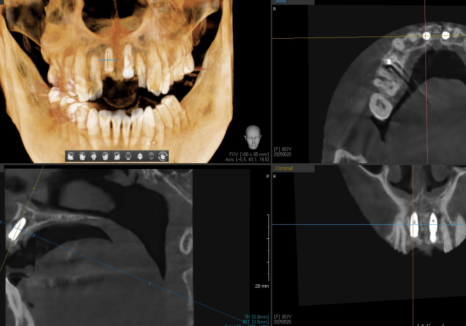

식립 후에도 촬영해서 의도한 대로

정확하게 들어갔는지 한 번 더 확인합니다.

250609

4개월 후 임플란트가 뼈와 잘 유착되었는지

확인하기 위해 기계로 수치를 재어본 뒤

높은 수치가 나온 것을 확인하고

보철을 제작하기 위해 본을 뜹니다.